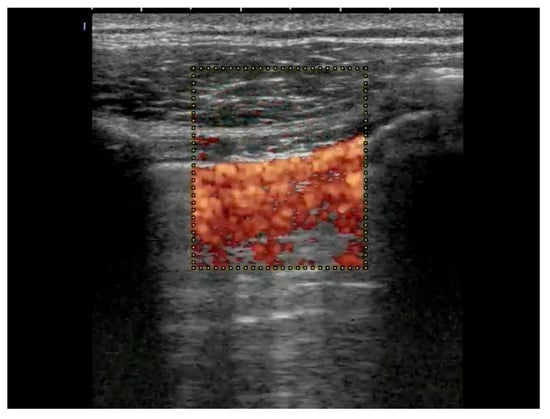

Linear transducers will deliver the best depiction of the pleural line, with convex ones delivering a wider but less detailed view [,]. To detect a pneumothorax, the patient must be in a supine or half-sitting position (30–45 degrees). The position of the probe is parasagittal on both sides of the sternum on two rib interspaces close to the highest point of the thorax and on the anterior axillary line. Confirming lung sliding (sliding lung sign) is the first scanning task. The confirmation of visceral and parietal pleural movement in opposite directions is achieved by saving a cine loop, an image using M-Mode (seashore sign). If sliding cannot be definitively confirmed, the next step is to look for vertical artifacts and the lung pulse. Such vertical artifacts typically originate from the pleural line and will usually not be seen in the presence of a pneumothorax at that location. Lung pulse excludes the presence of pneumothorax at that location, but may indicate a lack of ventilation of the affected side. It can be visualized with M-Mode or color Doppler at and slightly below the pleural line (color sign). Of note, lung sliding, typically occurring in the top 2 to 4 cm of the image, is usually not seen as clearly with a sector transducer when compared with linear or large convex probes [,,,] (Table 5, Figure 1, Figure 2 and Figure 3).

Color below pleural line means that there is movement because of breathing or lung pulse because of heart action.